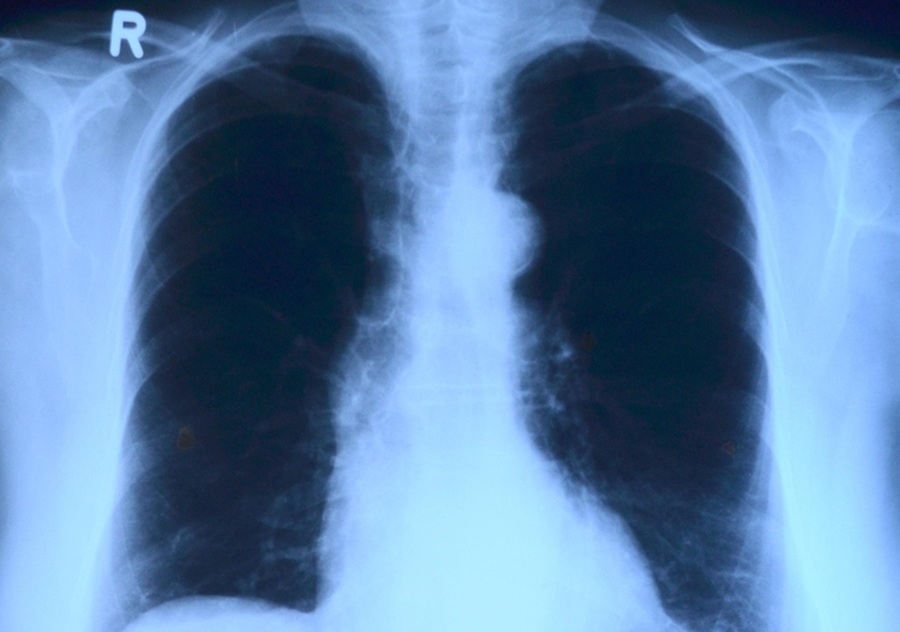

Bolest može zahvatiti različite organe, ali se u najvećem broju slučajeva razvija u plućima. Važno je naglasiti da jedna neliječena osoba može zaraziti veći broj ljudi u svojoj okolini, zbog čega je ključno rano prepoznavanje simptoma i pravodobno liječenje.